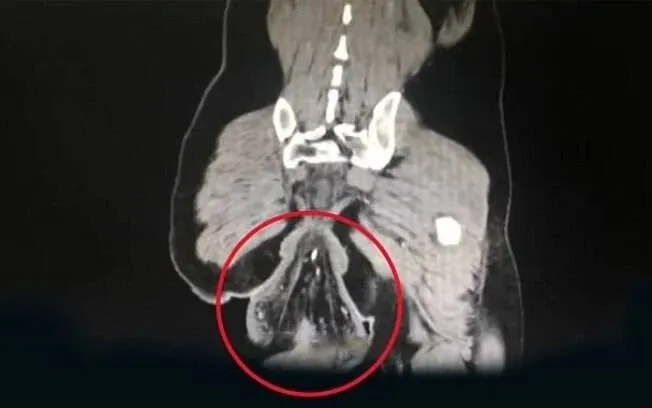

O diagnóstico foi de prolapso retal, uma condição rara e grave em que a parte final do intestino grosso perde sua sustentação e se exterioriza pelo canal anal. A situação do paciente foi considerada séria pela equipe médica, pois o reto ainda permanecia parcialmente preso ao corpo, mas já completamente fora do lugar.

Segundo Su, o paciente já convivia com episódios recorrentes de prolapso retal desde os quatro anos de idade. “A protuberância era capaz de se retrair por conta própria no passado”, afirmou. No entanto, como nunca procurou tratamento adequado, a condição se agravou com o tempo e acabou culminando no incidente mais severo.